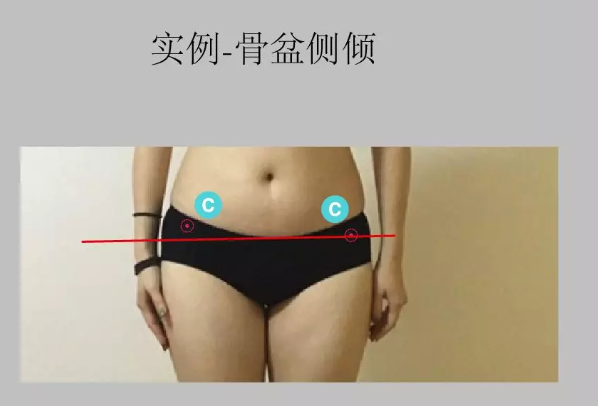

想象身体正中间有一根竖线。正常状态下经过眉心、鼻尖、胸锁关节重心、肚脐及会阴处。从正面观能发现的体态问题如下:· 骨盆侧倾:观察骨盆左右两侧高度是否一致,一般观察骨盆两侧的髂前上棘的高度。骨盆侧倾可能源于下肢的问题,也可能源于骨盆本身的倾斜。同时,骨盆侧倾可能导致高低肩,并增加脊柱 侧弯 的几率。